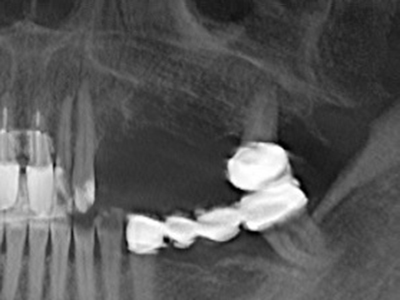

Fig. 17: Tomografía computarizada de un osteoma de crecimiento progresivo ...

Fig. 17b: justo al lado del canal alveolar con irritación nerviosa (vista lateral y coronal).